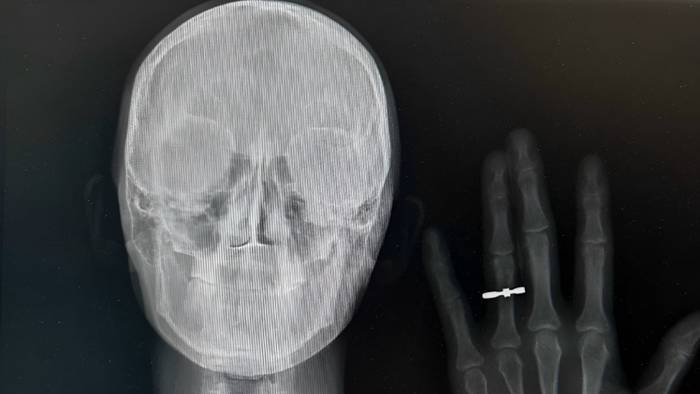

Рентгеновский снимок молодоженов из Новосибирска Кристины Шрайнер и Станислава Ефремова

Рентгеновский снимок молодоженов из Новосибирска Кристины Шрайнер и Станислава Ефремова / Фото: Предоставила Кристина Шрайнер

Предложение руки и сердца и свадьба — пожалуй, самые важные моменты в жизни каждой пары. Можно ли сделать их еще более запоминающимися? Пара медиков запустила новый тренд: они сделали рентген с обручальными кольцами. Об этой и других необычных свадебных задумках узнала «Вечерняя Москва».

Фото — рентгеновский снимок с рукой и кольцом на безымянном пальце — быстро разлетелось по сети. Оказалось, что так медики решили сообщить своим друзьям о предстоящей помолвке.

В 2023 году такую задумку решилась повторить пара врачей из Владивостока. А недавно подобный снимок сделали и другие молодожены, также преданные медицине, но уже из Новосибирска. Как раз они и прославились в сети.

— Мы оба врачи. Я работаю эндоскопистом, а мой жених Станислав — рентгенологом. Предложение он мне сделал в домашней обстановке. Сообщить родным, которые долго ждали этого события, хотелось красиво. Эта идея показалась нам очень символичной, — рассказывает невеста Кристина Шрайнер.